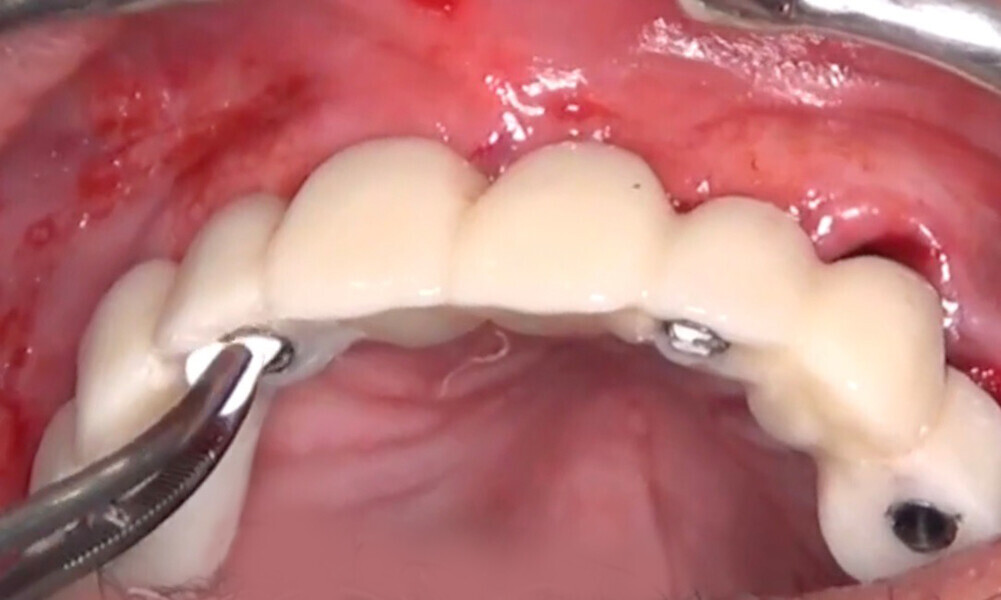

Four months later, we proceeded with the final prosthetic procedure based on clinical and radiographic evidence confirming osseointegration. The case was completed using Straumann RevEX scan bodies for a full monolithic design with a completely digital workflow. First, an intra-oral scan of the opposite arch was taken, followed by an intra-oral scan with the screwed-in temporary abutments. An intra-oral bite scan and an intra-oral scan of the soft tissue with the screw-retained abutments in place were then taken. The reverse scan bodies were attached to the provisional prosthesis, which was scanned extra-orally. Next, the prototype and verification jig were designed, followed by the milling of the prototype and verification jig (Figs. 45 & 46).

During the next visit, the milled prototype and verification jig were tried in, and the design and manufacturing of the final prosthesis were completed (Figs. 47 & 48). The final abutment utilised was Variobase for bridge (Straumann), placed on top of the screw-retained abutments. The material chosen for the final prosthesis was monolithic zirconia (Figs. 49 & 50).